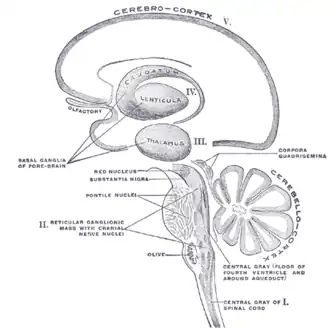

Schematic representation of the chief ganglionic categories (I to V).

Schematic representation of the chief ganglionic categories (I to V). -